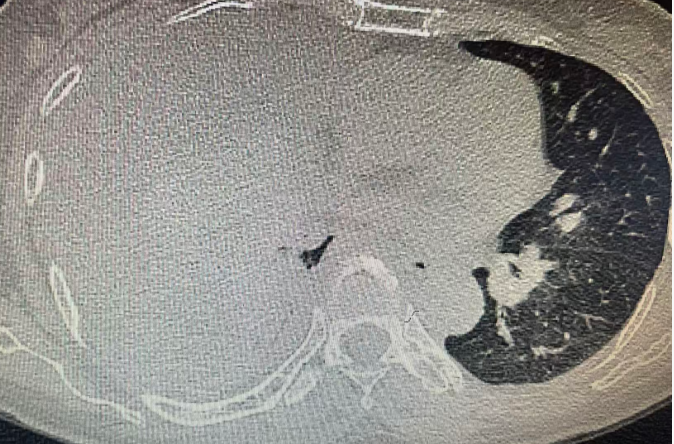

患者三个月前开始咳嗽,近一个月加重并出现活动后气促。外院曾按“肺炎、胸腔积液”治疗,症状暂时缓解后出院。但好景不长,咳嗽气促再次发作,且比之前更为严重。入院后CT检查结果令人震惊:右侧大量胸腔积液!患者和家属充满困惑:到底是什么原因导致胸水反复出现?接下来又该如何治疗?

患者入院后立即进行了胸腔穿刺引流,并将胸水标本送检。病理结果令人揪心:(胸腔积液)查见腺癌细胞最终诊断指向肿瘤!后续胸部增强CT检查发现右肺下叶结节并周围肺组织节段性肺不张,考虑周围型肺癌可能。至此,胸水反复生长的谜团终于解开——肺癌胸膜转移所致。